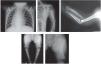

Patients present the following typical clinical and radiological findings: a round and flat facies with a prominent forehead, frontal bossing, short nose with a depressed broad bridge, short columella, anteverted nostrils, long philtrum and small chin. A rhizomelic shortening and radial head dislocation that leads to a characteristic limited extension of the elbows are observed. They also present a short and broad chest, widely spaced nipples and, in males, criptorchidism is frequent. Mental retardation was reported in four patients and delayed motor development occurred in a few cases. Skeletal findings are confined to the limbs with shortened humeri with hypoplastic condyles and axial rotation of their shafts. At birth, radius and ulna are short and thick, but straighten with age. Likewise, in newborns, the humerus is shorter than the radius, but with age it becomes longer. The radial head is anteriorly and laterally dislocated, the ulna is abnormally placed resulting in a radioulnar diastasis. Femora show bulky proximal ends and a distal hypoplasia, remaining relatively short with age, but the distal tapering decreases due to metaphyseal widening and decreasing outward rotation of the femoral shafts. The tibia and fibulae are moderately short and the epiphyseal ossification centers of the femora and tibiae are strikingly flat.

A detailed skeletal survey was performed revealed shortened humeri with abnormal sloping of the distal articular surface, shallow olecranon fossae with partially subluxed radii and radioulnar diastasis; short femora with metaphyseal widening and small laterally displaced patellae. Other bones and growth structures were normal.